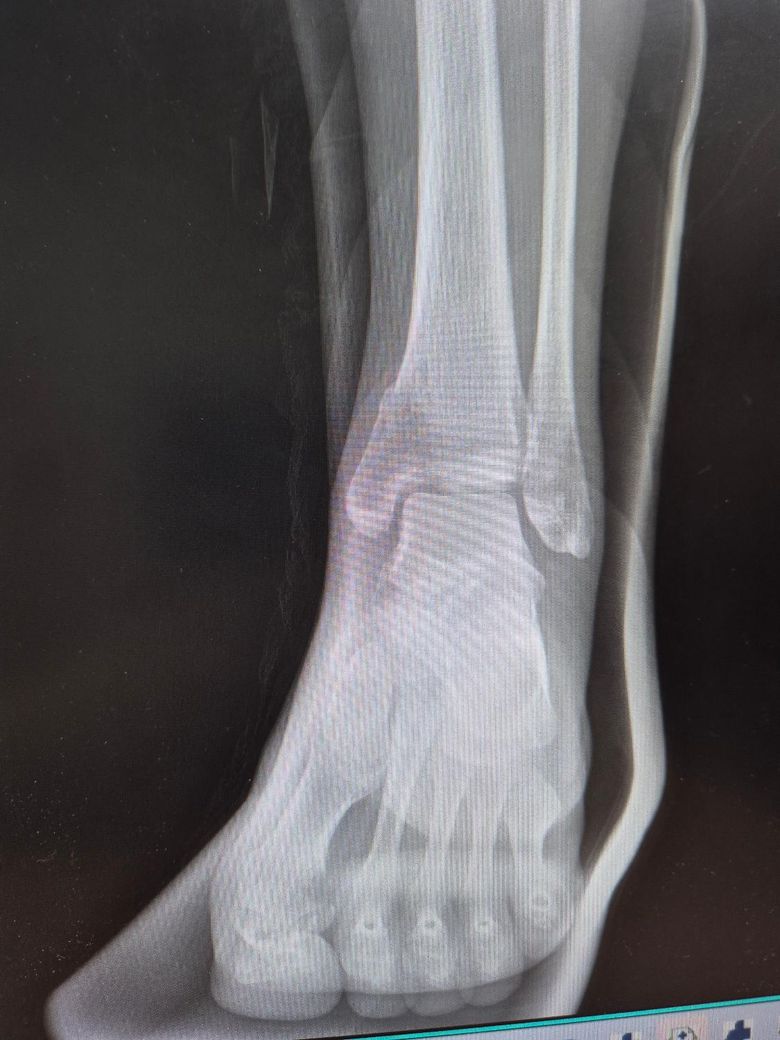

4월 16일 운동하다 다쳤고 밤이라 4월 17일 병원 가서 내측 복사뼈 골절 진단받았습니다.

붓기가 너무 심해서 1주일동안 고정시키고 상태보자고 했고 4월 24일 비수술 하기로 하면서 통깁스 시작했습니다. 6월 5일 6주간의 통깁스 마치고 2주 동안 반깁스 붕대로 했는데 6월 19일부터 붕대대신 벨크로로 변경하자 하셔서 변경했어요.

아래 사진은 6월 19일 찍은 사진입니다

• 2번 째 사진

현재 엑스레이 상으로 내측 복사뼈의 골절부는 어느정도 유합된 사태로 보이고 정형외과에서도 반깁스에서 벨크로로 전환을 권한 것을 보면 점진적 체중 부하를 시작해도 괜찮은 회복 단계로 판단됩니다!